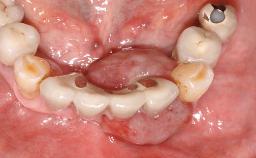

Oral implants are highly successful and offer long-term benefits, especially in the rehabilitation of edentulous patients or patients with oral defects following ablative tumor surgery (Albrektsson and coworkers 1986), and also after radiation therapy (Schiegnitz and coworkers 2014). With the number of implants placed globally going into the millions, implant dentists have observed some rare adverse events. Although carcinogenesis around implants is an exceedingly rare phenomenon, we recently reported about 15 patients treated for carcinomas adjacent to implants at our clinical department over a period of fifteen years (Moergel and coworkers 2014). The following case represents a patient of this cohort; it discusses possible risk factors and makes suggestions for a recall schedule. A 70-year-old woman was referred to our outpatient department for evaluation of a rapidly growing macroscopic alteration of the mucosa in the left mandible.